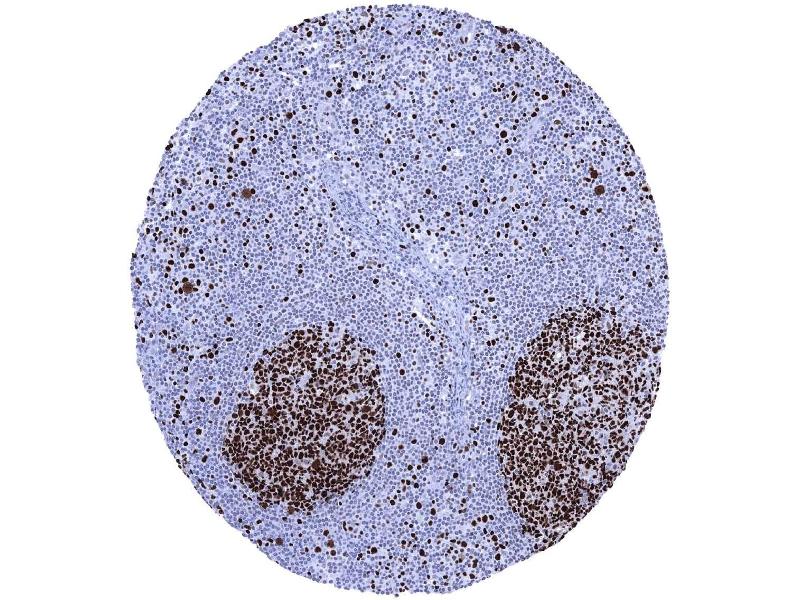

Positive Control: Colon: A strong nuclear MCM7 immunostaining should be seen in virtually all crypt base cells.

Product Description: MCM7 antibody validated for immunohistochemistry on 76 different Normal Tissues

Negative Control: Colon: MCM7 immunostaining should be largely absent in surface epithelial cells and in most stroma cells.